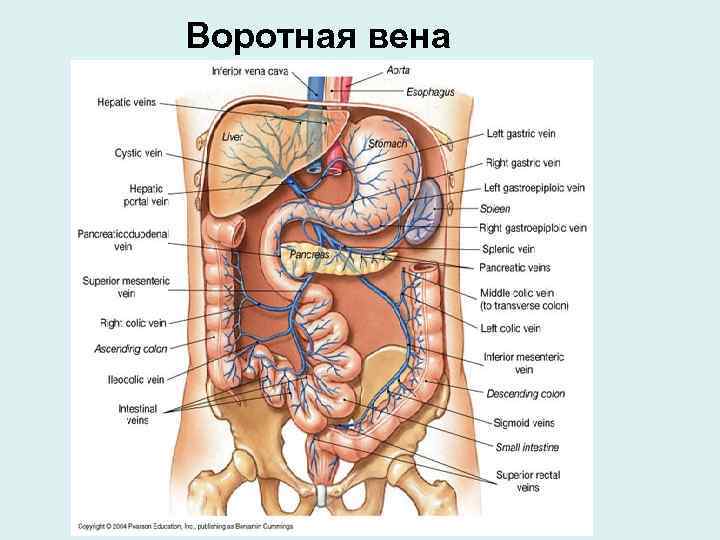

Воротная вена • Собирает кровь от непарных органов брюшной полости • Истоки (корни): селезеночная вена, верхняя и нижняя брыжеечные вены • Притоки: желудочные правая и левая, препилорическая, околопупочные вены

Воротная вена

Портокавальные и портокавальный анастомозы • Пищеводное сплетение – анастомоз между корнями левой желудочной вены и пищеводными венами Левая желудочная вена воротная вена Пищеводные вены верхняя полая вена (через парную и полунепарную)

Прямокишечное сплетение • Верхняя прямокишечная вена впадает в воротную вену (через нижнюю брыжеечную) • Средняя прямокишечная вена – во внутреннюю подвздошную • Нижняя прямокишечная – во внутреннюю половую - во внутреннюю подвздошную вену

Пупочное сплетение • Околопупочные вены воротная вена • Верхняя надчревная верхняя полая (через внутреннюю грудную и плечеголовную) • Нижняя надчревная нижняя полая вена (через наружную и общую подвздошные)

Мезоперитонеальные вены • Соединяют ободочные вены – притоки системы воротной вены и поясничные вены – притоки нижней полой вены